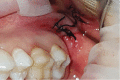

Gingival recession is an oral health problem that affects a large part of the population. Several treatments are suggested in the current literature; among them is the use of buccal fat pad grafting. The objective of this case report is to describe the treatment of a Miller Class I gingival recession using a nonpedicled buccal fat pad graft immediately after performing the surgery for buccal fat pad removal (bichectomy technique). First, bilateral surgical removal of the buccal fat pad was performed with the main objective of eliminating oral mucosa biting. The recipient site was prepared to receive a portion of the fat pad that was cut and macerated in a size that was sufficient to cover the recession. The patient was followed up at 15, 30, 60, and 365 days postsurgery, and the results showed an elimination of the oral mucosa biting and complete coverage of the gingival recession. It was concluded that the nonpedicled buccal fat pad graft is another option for the treatment of Miller Class I recessions.